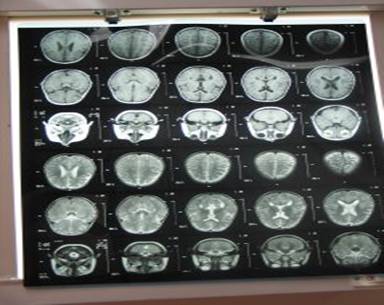

The patient underwent brain CT scan on the third day of

operation. The report was:

Subdural effusion with few isodense areas in both frontal lobes.

Figure (2)

The patient underwent a second brain CT scan on day 14 of

treatment. Brain scan reported: There is evidence of abnormal

frontal lobe bilaterally more prominent on the left side. Fluid

collection with mild mass effect in left frontal area (epidural

empyema).

Figure (3)

Figure(4)

After 4.5 months of treatment: laboratory findings and brain

CTscan had become normal.